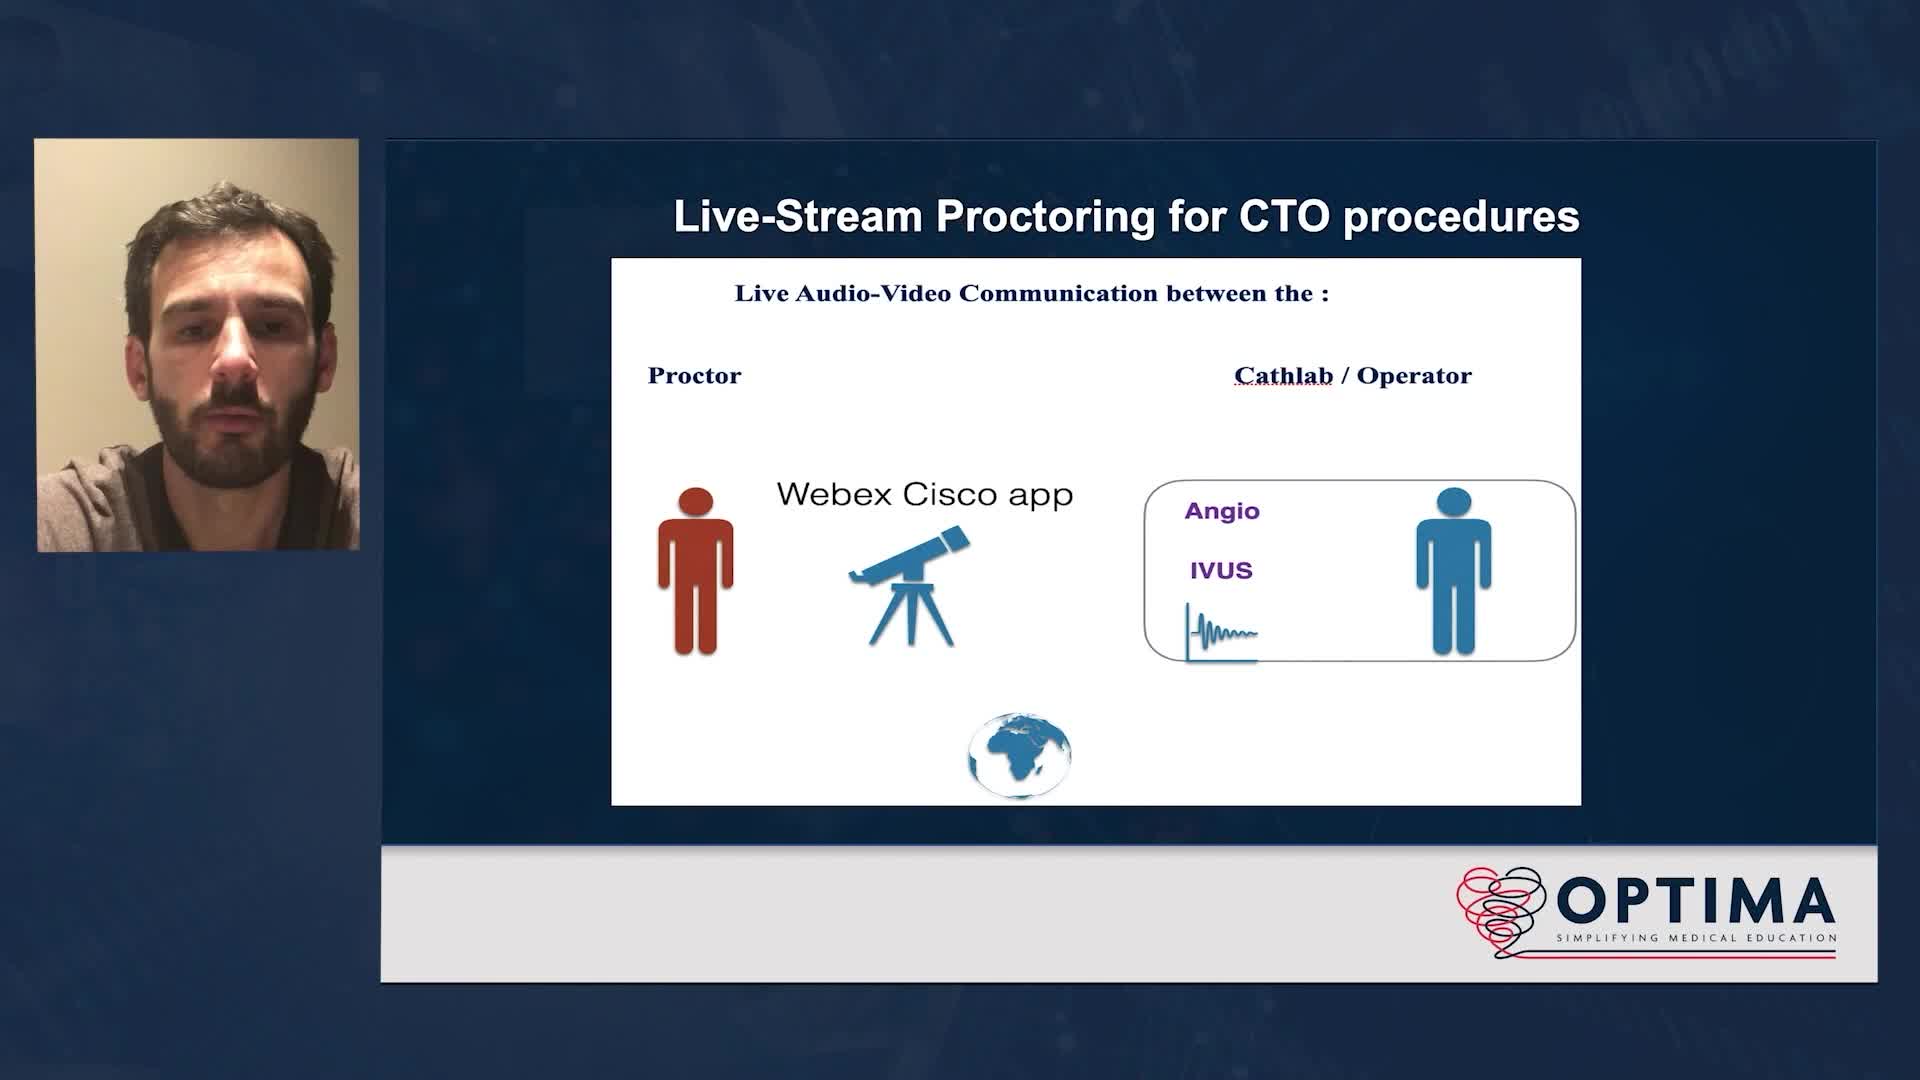

Gulf-Optimal Chronic Total Occlusion: Bahrain Event - Day 1

Gulf-Optimal Chronic Total Occlusion: Bahrain Event - Day 2

Gulf-Optimal Chronic Total Occlusion: Live Case Follow Up